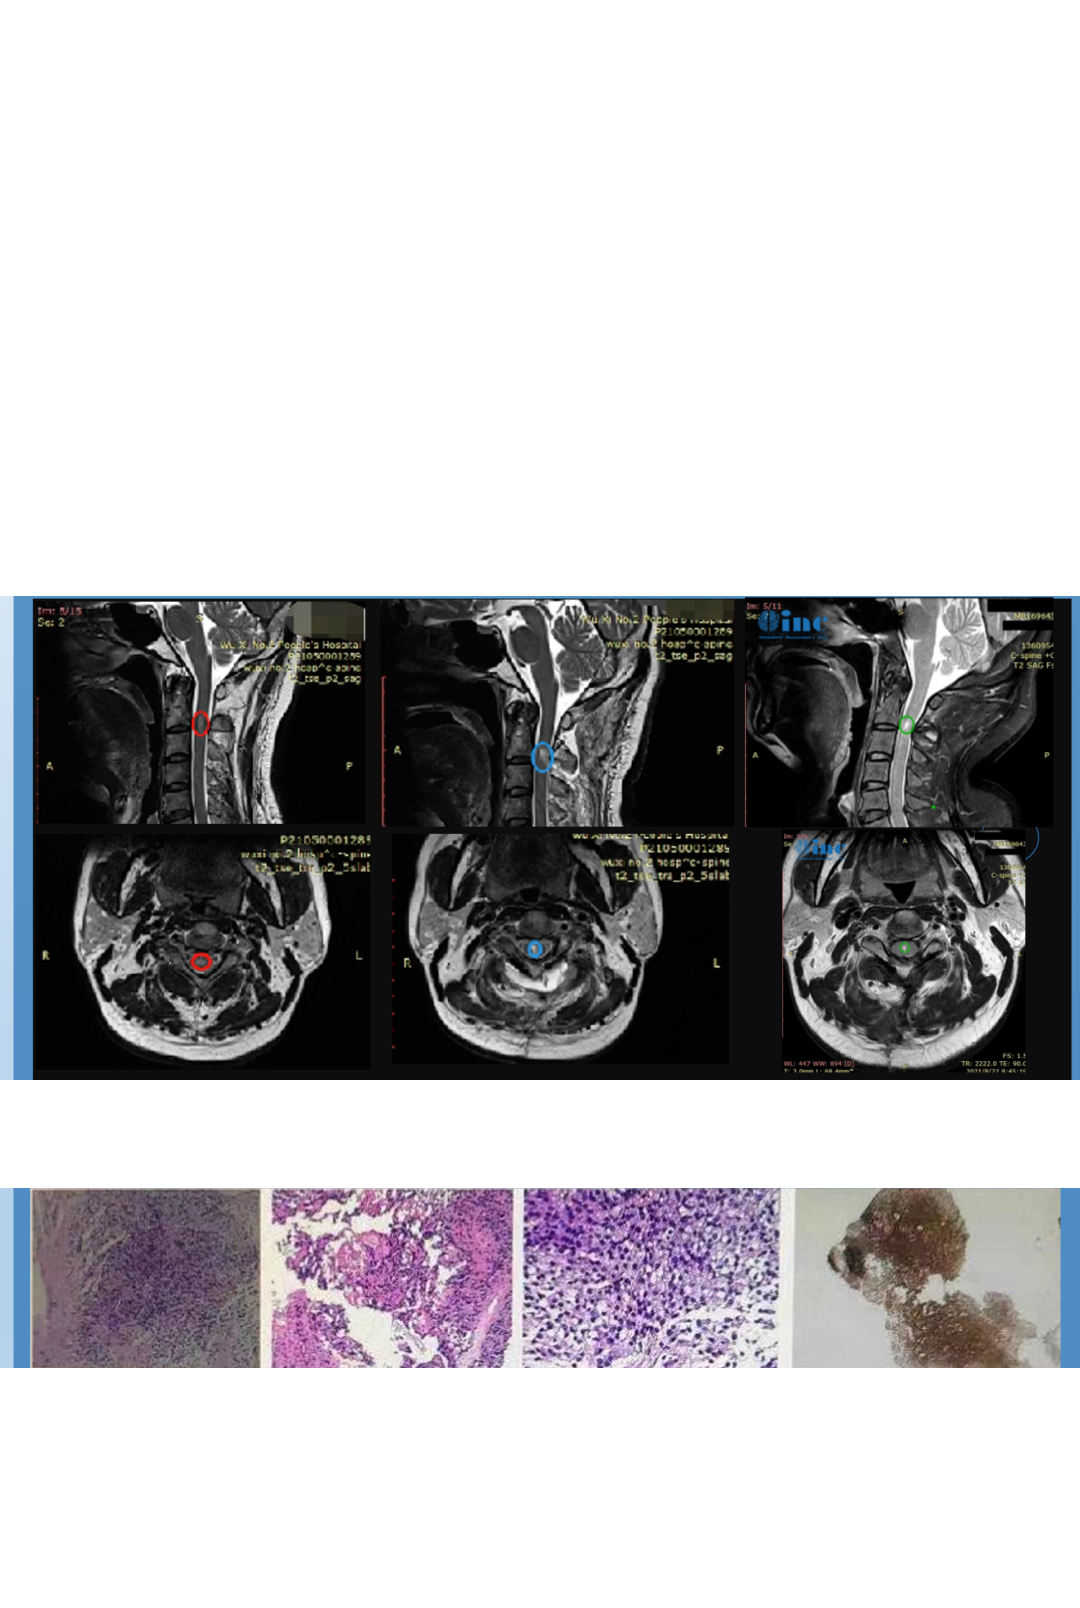

术前术后影像对比显示:脊髓内星形细胞瘤的瘤体强化部分被完整切除,肿胀效应减轻。